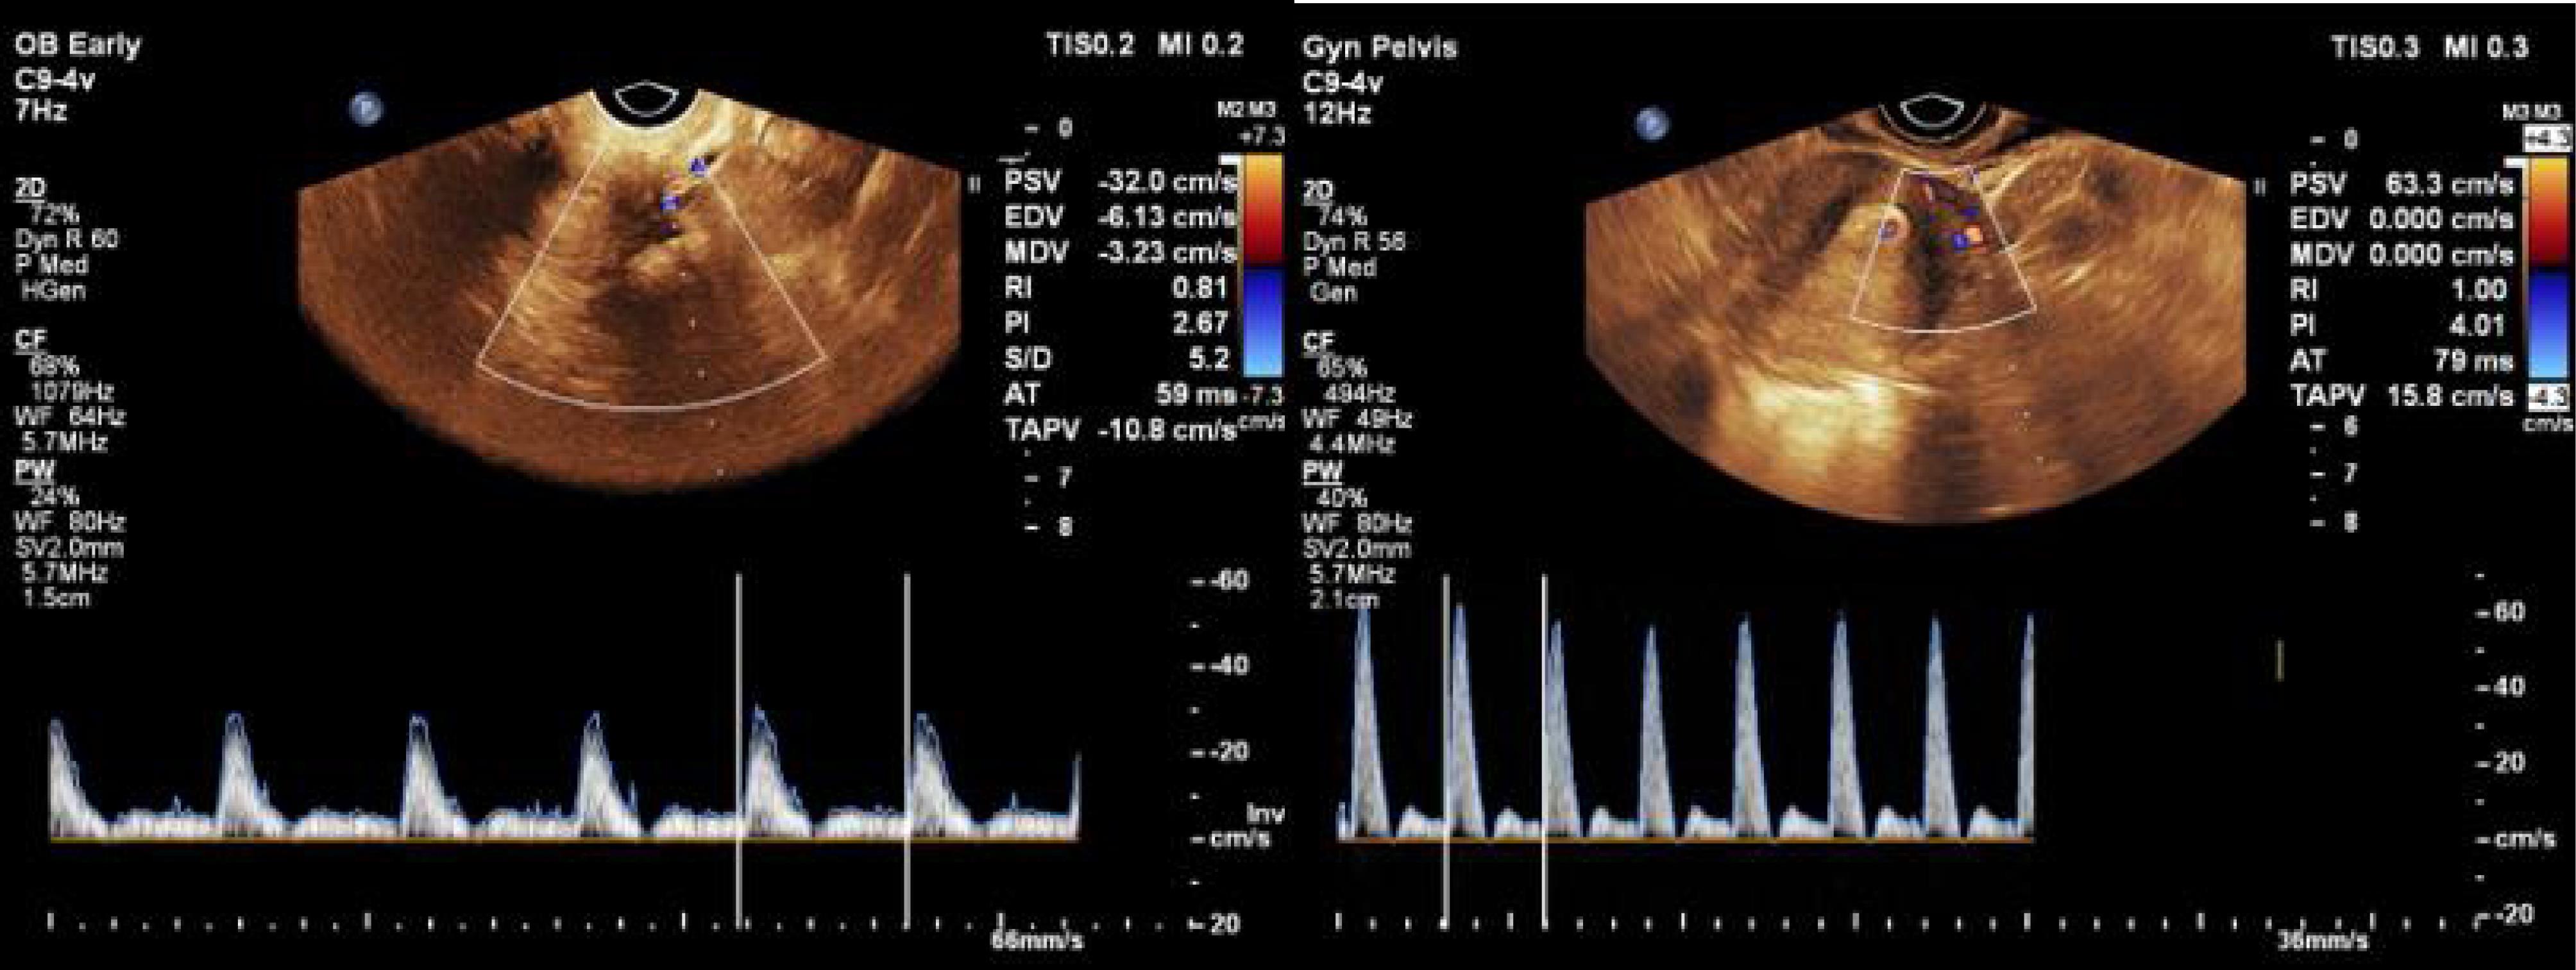

The data analysis demonstrated that RI values were significantly higher at all the follow-up time points compared with the previous time point, while serum β-hCG levels were significantly lower (Figure 1, Table 2). Moreover, sac diameter values increased 72 hours post-treatment, then represented a reduction.

Figure 1.

RI Measurement From the Closest Myometrial Artery Adjacent to the CSP Before (a) and After (b) Treatment. Note. RI: Resistive index; CSP: Cesarean scar pregnancy. The results show an increase in the amount of RI from 0.81 to 1 following medical treatment